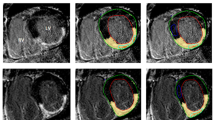

T1 maps were generated by three points pixel-wise curve fitting [28] and stored in Digital Imaging and Communications in Medicine (DICOM) Format. To extract myocardial T1 value, endocardial and epicardial contours were manually traced using QMass MR 7.2 (Medis, Leiden, Netherlands), and the myocardial circumference was divided into segments according to the American Heart Association 17-segment model [29]. Care was taken to exclude epicardial structures and blood from the contours. T1 value of the blood pool was measured by manually drawing a region of interest in the left ventricular cavity excluding papillary muscles. The image quality for all segments was visually rated using a scale in which a score of 3 indicated that image quality was good, with no artifacts; a score of 2, that image quality was satisfactory, with minor artifacts; and a score of 1, that an image was non-evaluable with major artifact, as described by Messroghli [30]. T1 values from segments that were rated as non-evaluable were excluded from analysis. ECV and λ values were calculated according to the following formulae [15]:

Study subject characteristics are given in Table 1. CMR was well tolerated by all subjects in the study. Both ECV and λ were significantly higher in the heart failure group compared to the healthy group (ECV: 0.287 ± 0.034 vs. 0.267 ± 0.028, p = 0.002; λ: 0.481 ± 0.052 vs.442 ± 0.037, p < 0.001). For the healthy group, there was no statistical difference between 12 minute and 25 minute ECV and λ (ECV: 0.264 ± 0.028 vs. 0.271 ± 0.028, p = NS; λ:0.436 ± 0.038 vs. 0.447 ± 0.037, p = NS). In addition, there was no significant difference for these parameters between gadopentetate dimeglumine and gadobenate dimeglumine (ECV: 0.271 ± 0.027 vs. 0.264 ± 0.029, p = NS; λ: 0.449 ± 0.039 vs. 0.435 ± 0.035, p=NS). Similarly, there was no statistical difference between 12 minute and 25 minute ECV and λ (ECV, 0.282 ± 0.033 vs. 0.289 ± 0.034, p = NS; λ: 0.475 ± 0.053 vs. 0.487 ± 0.051, p = NS) in the heart failure group. These results confirm the stability of ECV over moderate time intervals, and suggest a similar biodistribution of the two contrast agents. Of note, the image quality of T1 maps was significantly better in healthy group (2.8 ± 0.2 for healthy, 2.6 ± 0.4 for heart failure, p < 0.001).